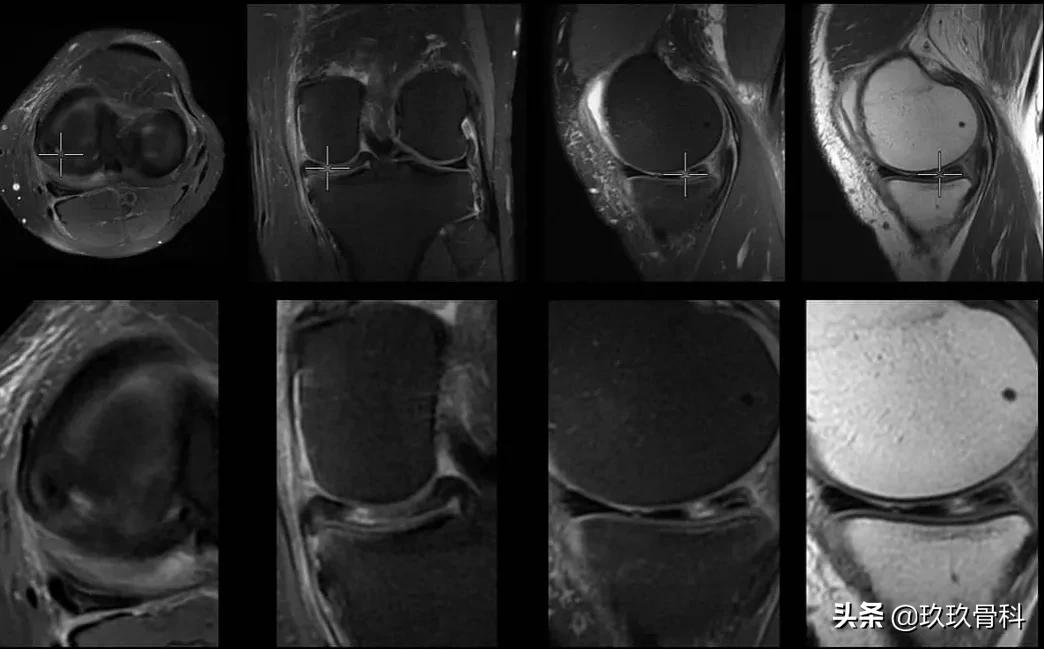

膝关节核磁共振可以半月板损伤分级:

△ 核磁共振下半月板形态

I级损伤

半月板内球状或椭圆形高信号,不与半月板的关节面相连,多见正常人或轻度退变者,无需治疗;

II级损伤

是I级损伤的进一步发展,半月板内高信号延伸至半月板关节缘,仍未及关节面,脆性增加。故半月板退变者易在运动或者突然旋转动作时损伤半月板,多见于退变或轻度外伤,多不需要治疗;

III度损伤

半月板内高信号波及关节面,表现为全层、斜裂、水平、混合撕裂影,半月板正常形态消失;多有手术指征。